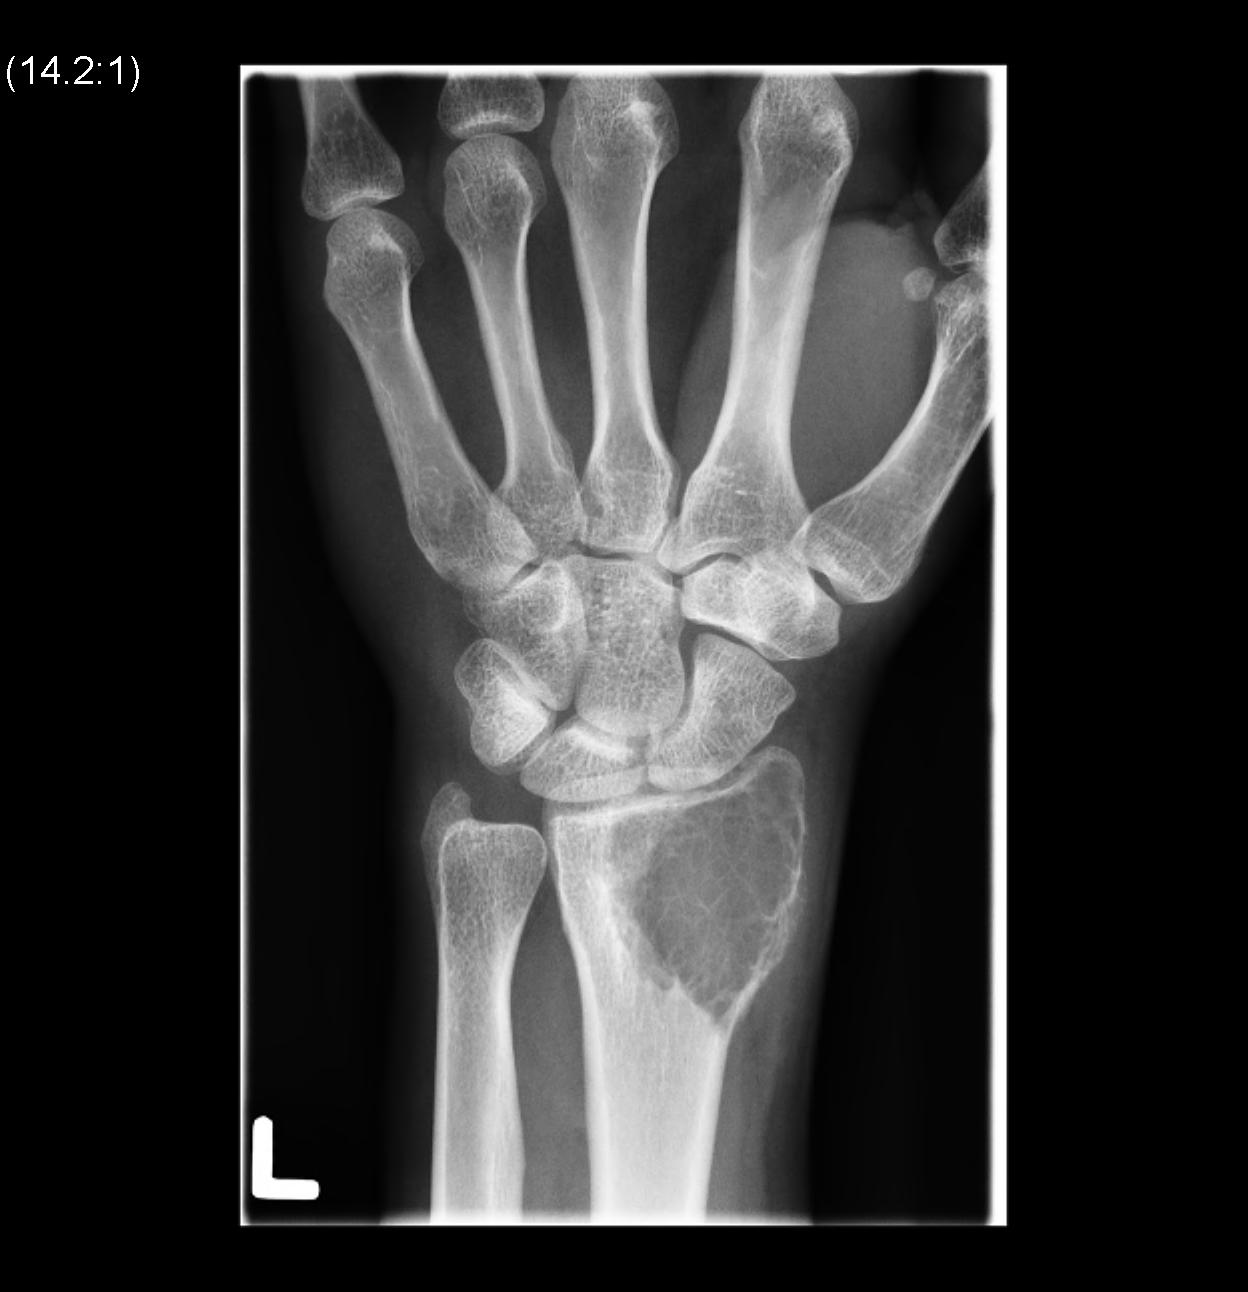

Wrist / Hand

Carpus / metacarpal / phalanges - dorsal approach